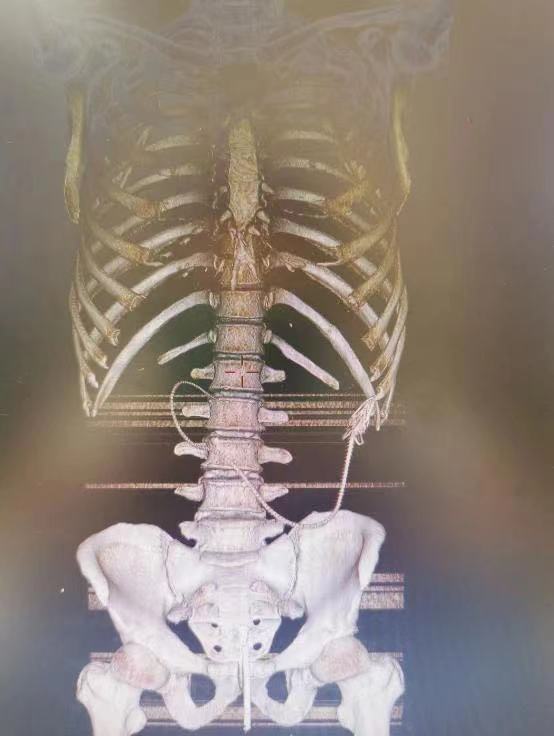

医生通过X光片进行检查,发现黄鳝已经如进入腹腔,于是立即安排手术,把黄鳝从男子的腹腔里取出,这条黄鳝非常大,足足有20多厘米,如果男子来得再晚一点,后果不堪设想。

从曝光的X光片看,黄鳝的头部已经到了肋骨附近,真的是非常危险,如果黄鳝攻击其它脏器,男子恐怕是凶多吉少。